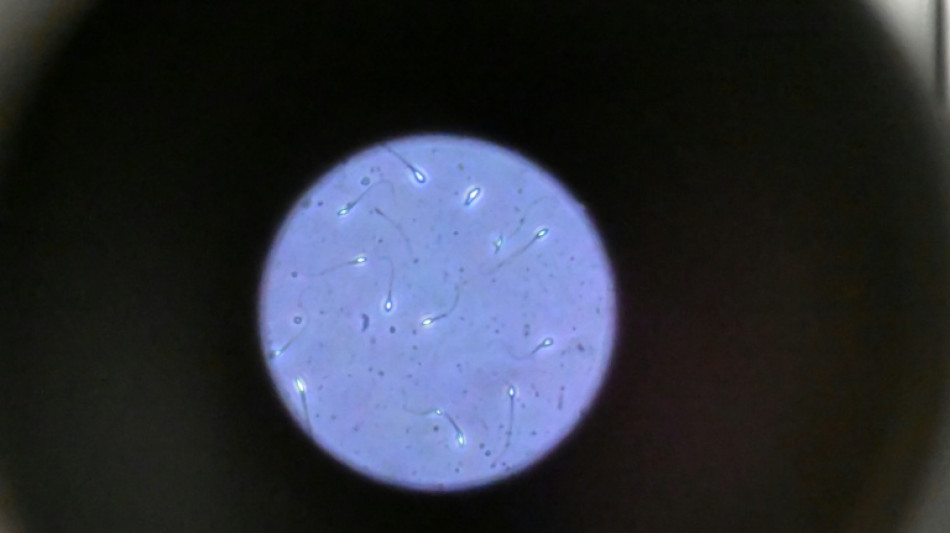

Dans l'espace, les spermatozoïdes ont du mal à trouver leur chemin / Photo: Damien MEYER - AFP/Archives

Dans l'espace, les spermatozoïdes ont du mal à trouver leur chemin vers l'ovule en raison de la microgravité, qui perturbe aussi le développement des embryons, selon une étude publiée jeudi dans Communications Biology.

"Les spermatozoïdes doivent activement trouver leur chemin vers l'ovule et cette étude est la première à tester leur capacité à le faire dans des conditions semblables à ce qui se passe dans l'espace", explique à l'AFP Nicole McPherson, autrice principale de l'étude et chercheuse à l'Université d'Adelaïde (Australie).

Les chercheurs ont testé successivement du sperme de souris et humain dans ce dispositif placé dans un appareil en constante rotation pour simuler la microgravité.

Les gamètes ont été environ 50 % moins performants pour naviguer à travers ce parcours que sous la gravité terrestre. Cela équivaut à une baisse de 30% du taux de fécondation réussie, selon les résultats de l'étude.